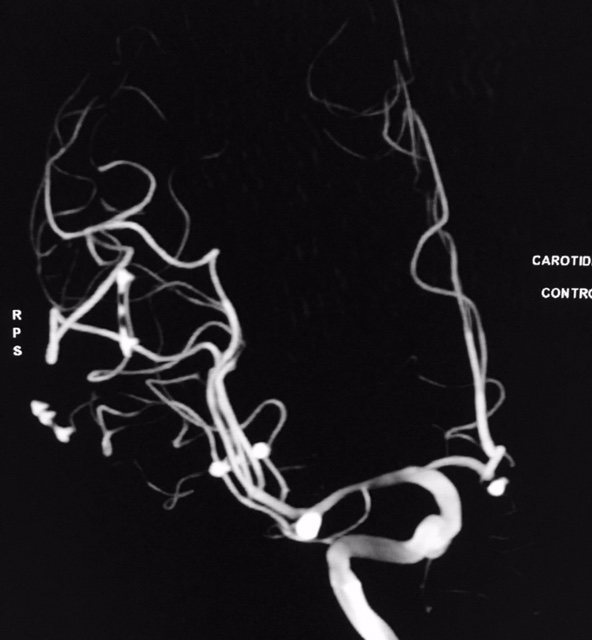

Tratamento de aneurisma cerebral com auxílio de balão duplo lumém e neurostent LEO